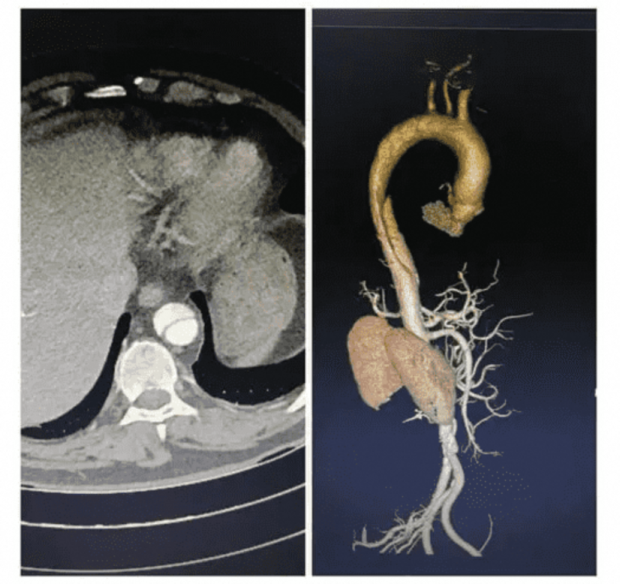

醫生點進去,不止能看到AI給出的AAS概率值,更重要的是,AI重建了血管三維圖像,勾畫出主動脈外壁和真腔,並且點出懷疑的病灶位置在哪裏。

比起直接拋給醫生一個結論,這樣顯然更能讓醫生理解AI為什麼得出這個結論,從而評估AI的結論有多靠譜。